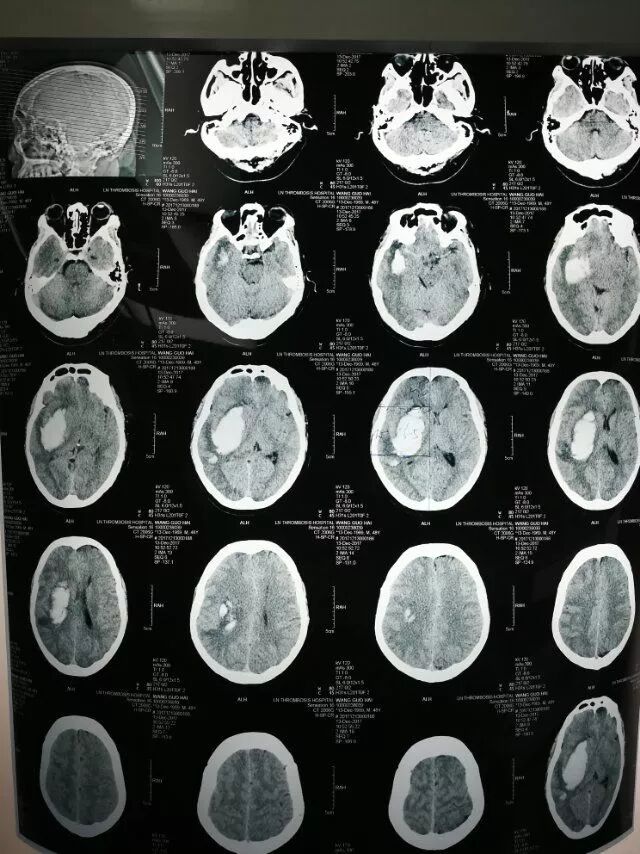

患者男性,53岁,以右侧基底节出血为诊断入院,量约50毫升。

术前片子

术后第一天复查,患者清醒,言语正常。